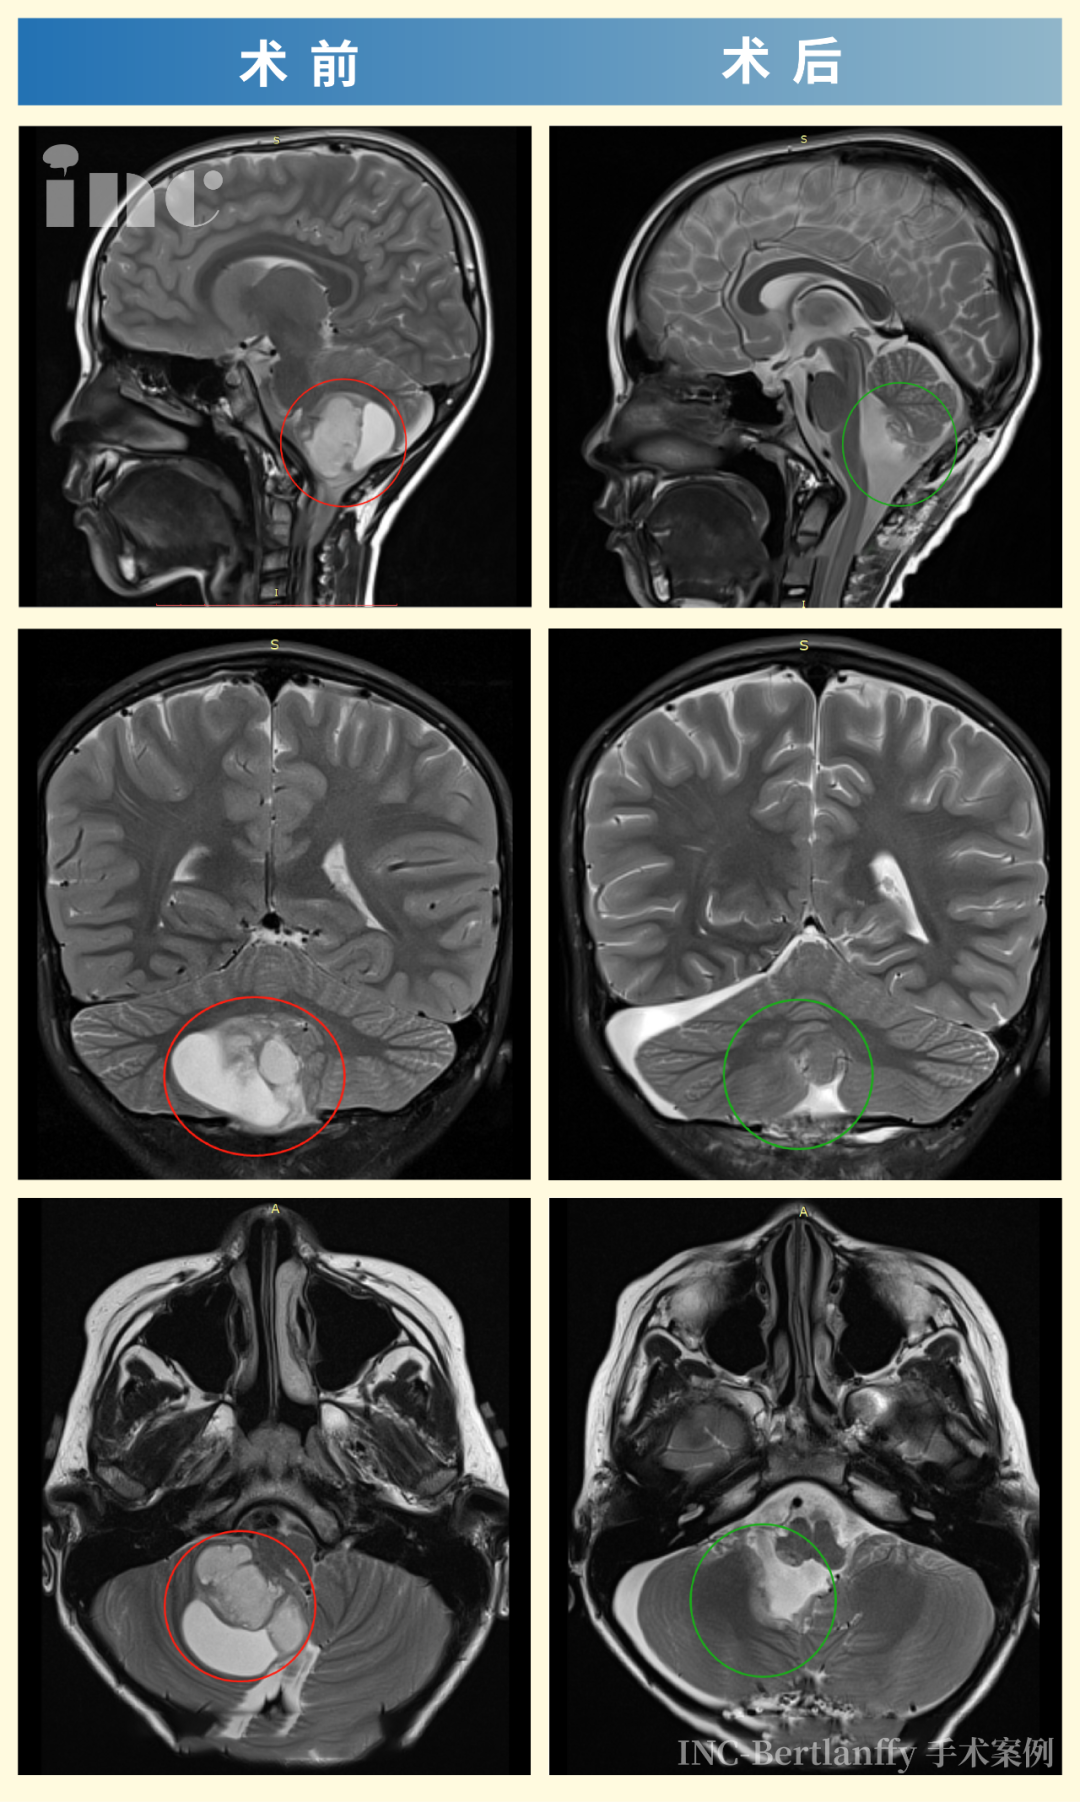

母亲立即带其就医检查,CT影像结果显示:小脑区域存在巨大占位性病变。进一步头部增强磁共振显示:右侧小脑半球见40mm×37mm大小异常信号灶,邻近第四脑室受压变窄,脑干受压,中线结构局部左移。临床诊断考虑低级别星形细胞瘤。

巴教授主刀采用正中枕下入路,最终实现肿瘤全切,手术过程顺利,无术中并发症。术后MR复查确认肿瘤完全切除无残留,肿瘤囊肿部分实行“开窗”术及囊壁切除,双极电凝彻底烧灼基底,周围正常脑组织得到保护,脑干获得充分减压,对中脑的挤压/移位压力显著减轻,小脑组织大部分复位。